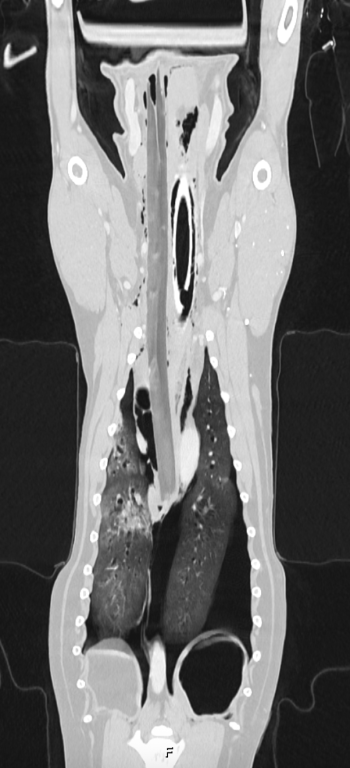

Mollie's CT scan

The five-year-old dog was running to get the stick, which had landed flat on the floor, when the end became stuck in the ground as Mollie tried to pick it up. It lodged under her tongue, travelling through her neck, close to the windpipe, and coming to a stop above her heart.

Small animal surgery resident Hilario Gonzalez Montano said: “Mollie was playing when she was impaled by a stick, which went around 40cm from inside her mouth to the chest, and stopped very close to her heart.

“The surgery was very challenging as the stick was close to critical structures like the heart, aorta, oesophagus, jugular vein and carotid artery.